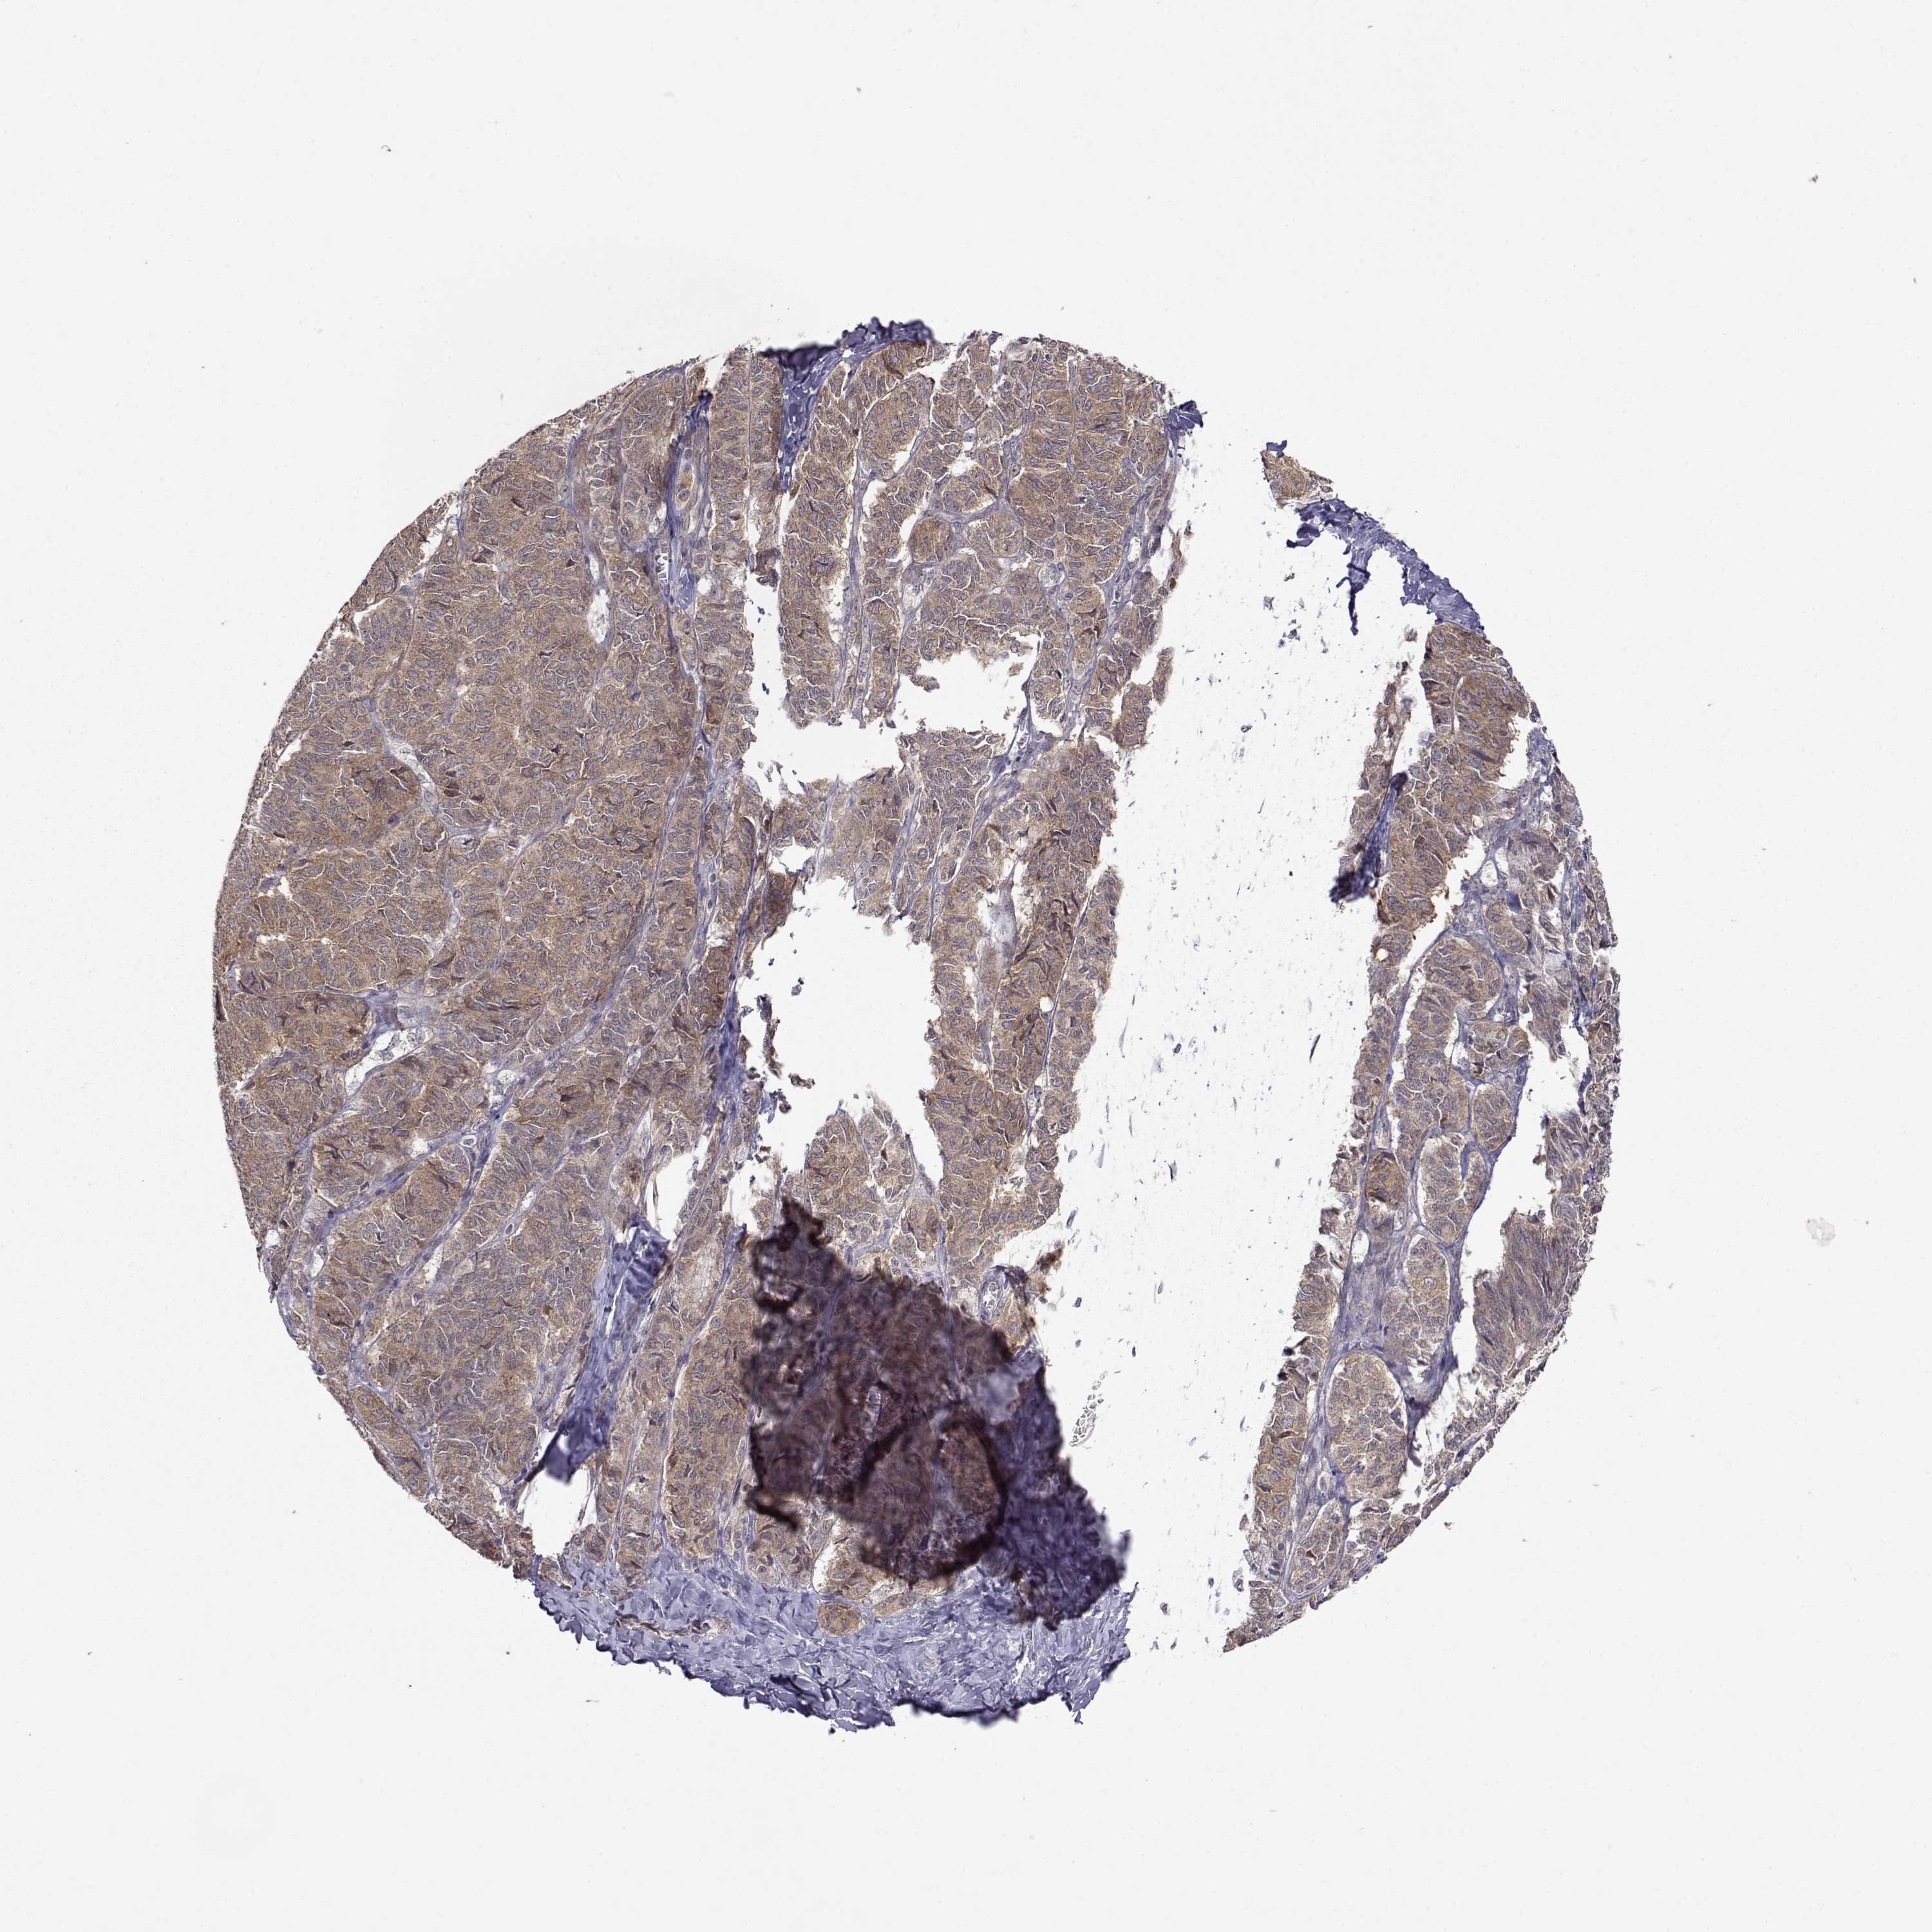

OVARIAN CANCER - Protein expressioni

A mouse-over function shows sample information and annotation data. Click on an image to view it in a full screen mode. Samples can be filtered based on level of antibody staining by selecting one or several of the following categories: high, medium, low and not detected. The assay and annotation is described here.

Note that samples used for immunohistochemistry by the Human Protein Atlas do not correspond to samples in the TCGA dataset.

Antibody stainingi

Antibody staining in the annotated cell types in the current human tissue is reported as not detected, low, medium, or high, based on conventional immunohistochemistry profiling in selected tissues. This score is based on the combination of the staining intensity and fraction of stained cells.

Each image is clickable and will lead to virtual microscopy that enables deeper exploration of all samples and also displays staining intensity scores, fraction scores and subcellular localization as well as patient and tissue information for each sample.

Antibody HPA073653

Staining

High

Medium

Low

Not detected

Intensity

Strong

Moderate

Weak

Negative

Quantity

>75%

75%-25%

<25%

None

Location

Nuclear

Cytoplasmic/membranous

Cytoplasmic/membranous,nuclear

Cystadenocarcinoma, serous, NOS

Cystadenocarcinoma, mucinous, NOS

Carcinoma, endometroid